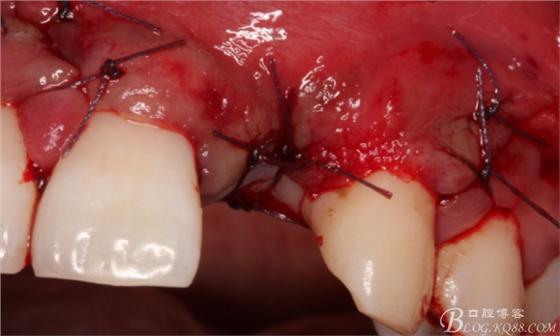

旋入一長(zhǎng)兩短3顆鈦釘。

將自體骨與BIO-OOS骨粉混合植到術(shù)區(qū),蓋生物膜。

縫合。